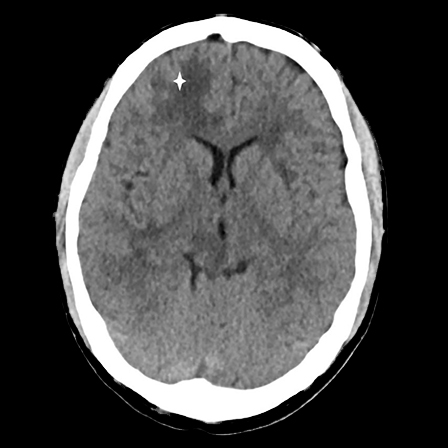

CT-undersøkelse uten kontrast av hodet ble tatt umiddelbart etter innleggelse og viste lavattenuerende forandringer i hvit substans frontalt i høyre storhjernehemisfære (fig 1) og i høyre lillehjernehemisfære. Supplerende magnetisk resonanstomografi av hjerne og medulla påfølgende dag avdekket multiple lesjoner i hjernestamme, lillehjerne og begge storhjernehemisfærer (fig 2). Nevroradiolog vurderte funn som forenlig med multiple metastaser, hjernetuberkulose, parasittsykdom eller septiske embolier med sekundær abscessdanninger. Spinalvæskeundersøkelse viste leukocyttnivå på 9 · 109/l, men ellers normale verdier for erytrocytter, glukose og protein. Det ble samme kveld utført CT av thorax, abdomen og bekken for å se etter tegn til ekstracerebral sykdom, inkludert kreft, bakterielt infeksjonsfokus, tuberkulose i eller utenfor lunger, eventuelt tegn til parasittsykdom. Denne avdekket multiple mikronoduli i lungene, mest i apikale deler av begge overlappene, én litt større nodulus apikalt og lateralt i venstre overlapp samt en liten høyattenuerende lesjon til høyre for avgangen av høyre hovedbronkus som var forenlig med en forkalket lymfeknute (fig 3). Det var multiple lavattenuerende lesjoner i abdomen og bekken, mest i øvre del av lever, og i tillegg lesjoner i nyre og prostata. Radiologen beskrev funnene som mest forenlig med miliær tuberkulose.